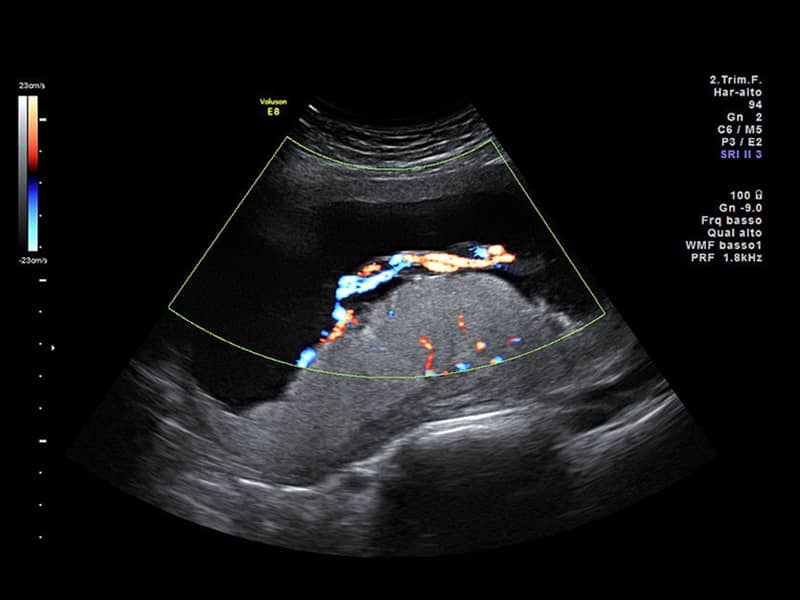

سپس یک مبدل یا کاوشگر بر روی پوست ناحیه شکم- لگن حرکت می کند که امواج صوتی با فرکانس بالا را به قسمت های بدن مادر و جنین می فرستد. این امواج صوتی به عقب منعکس می شوند و توسط دستگاه اولتراسوند ضبط می شوند و به تصویر یا نمودار تبدیل می شوند. این تصاویر توسط سونوگرافیک برای ارزیابی وضعیت شما تفسیر می شود.

هدف از اسکن آناتومی بررسی کامل کودک شما از سر تا انگشتان پا است. اندازه گیری های خاصی انجام می شود و اندام های قابل مشاهده یک به یک ارزیابی می شوند. ساختارهای اطراف بارداری مانند دهانه رحم، جفت، بند ناف و حجم مایع آمنیوتیک نیز ارزیابی می شوند.

سونو گرافی آنومالی مرحله دوم یا اسکن آنومالی یک روش بدون درد ، سریع ، غیر تهاجمی و ایمن است که برای تشخیص ناهنجاری های مادرزادی و ناهنجاری های رشد در جنین استفاده می شود. همچنین آسیب شناسی جفت را شناسایی می کند، به برنامه ریزی نحوه و زمان زایمان کمک می کند و ارزیابی می کند که آیا نیازی به ختم بارداری وجود دارد یا خیر.